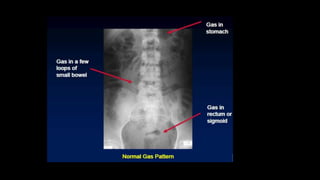

Erect Chest Supine abdomen Erect abdomen Left lateral decubitus

Demonstrates-

-Small pneumoperitoneum

-Chest abnormalities

-Acute abdomen complicated

by chest pathology

-Acts as a baseline

Shows-

-Distribution of gas

-Caliber of bowel

-Displacement of bowel

-Obliteration of fat lines

Shows air-fluid level If patient cannot sit or stand

-Free gas between liver and

lateral abdominal wall

-Gas filled duodenal loop

-Calcification in aortic

aneurysm